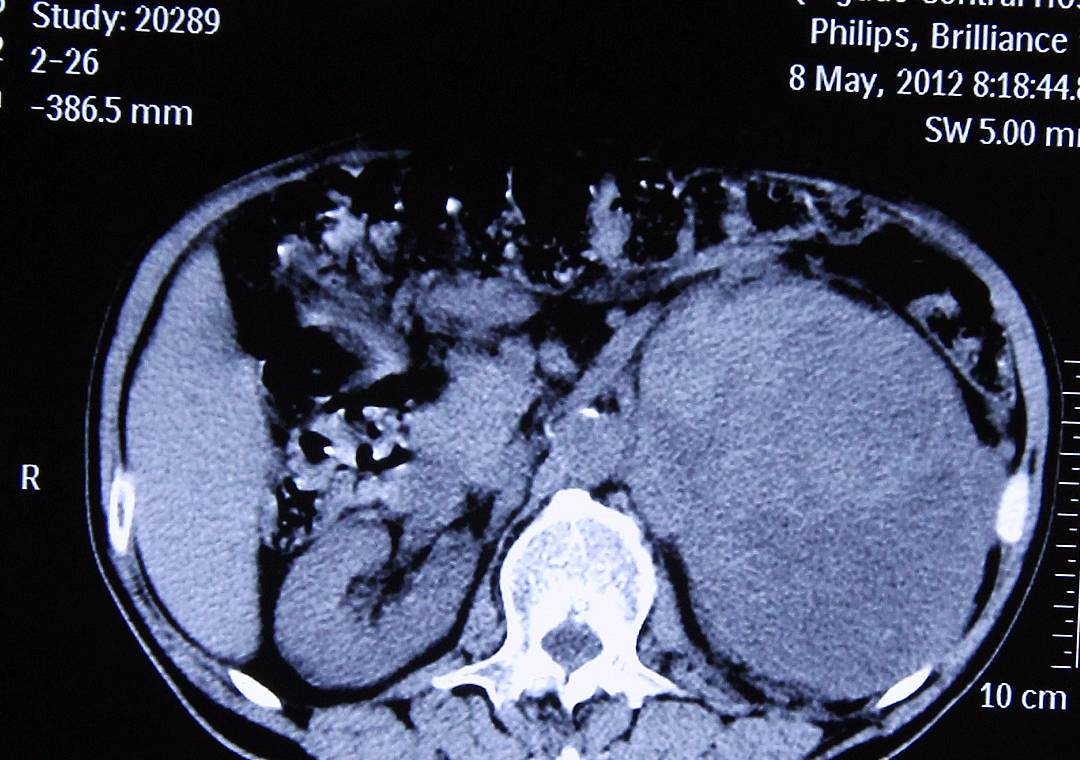

文章图片

1、控制原发病

通常是囊肿不会对身体造成太大的影响 , 甚至不会出现症状 , 但如果是有某些疾病导致的肾囊肿 , 则会根据原发病的病情而影响到身体健康 。 因此要治疗肾囊肿 , 首先要控制好其原发疾病 , 否则原发病不得到控制 , 肾囊肿在治疗后还是容易再次发作 。

2、减少刺激

肾囊肿一般不会出现明显的症状 , 但是如果囊肿破裂 , 还是会引起出血以及局部的感染 。 因此在生活中还需要减少对囊肿部位的刺激 , 尤其是外伤和剧烈运动都要注意不对囊肿部位造成损伤 , 其次饮食上保持清淡 , 避免辛辣刺激的食物影响到囊肿 。

3、穿刺

有些多发性的肾囊肿 , 可能会影响到肾脏功能 , 或者影响到周围组织而引起病变 , 因此可以对这种是囊肿进行穿刺抽液来保证控制疾病的发展 。 穿刺后还可以再破坏囊壁来避免囊肿复发 , 但需要注意治疗后的护理 。